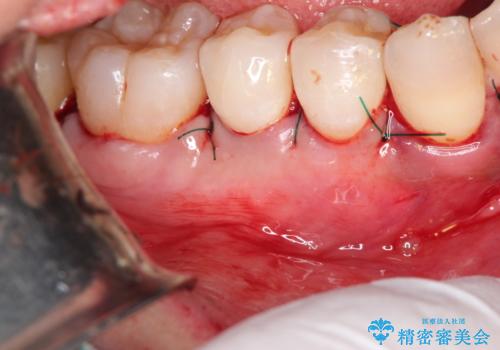

- 昔に受けた矯正治療がきっかけで歯肉が下がってしまった事を主訴として来院された患者様です。

結合組織移植術を行う方法を提案しましたが、傷口が口蓋にもできるのが嫌だとのことで、代替案としてバイオマテリアルを併用した根面被覆術を計画致しました。

治療対象部位は右下4,5,6番の3本です。